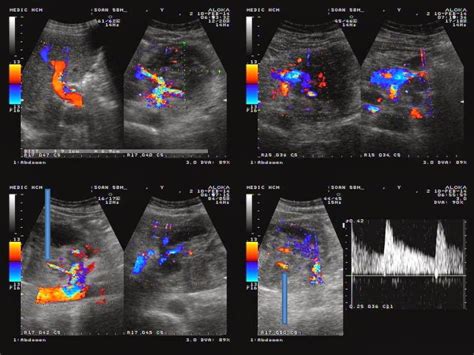

The epidemiological history, demographics data, clinical characteristics, laboratory data, treatment programs, and outcome measures were obtained from patients' medical records. Waveform image (bottom right) shows the sound of flowing blood in the carotid artery. Patient preparation and position for the ultrasound examination 4. Orl j otorhinolaryngol relat spec. Ultrasound in metastatic neck disease. · thyroid ultrasound, if not previously done. Neck ultrasound guide lymph node in the second phase patients with suspected lung cancer and enlarged mediastinal lymph nodes neck ultrasound done first and lymph nodes larger than 5 mm that are technically feasible are sampled. A solid one is more likely to have cancerous cells, but you'll still need more tests to find out. Its use is also limited in. If ultrasound examination of a patient with head and neck cancer reveals a lymph node that is increasing in size or new nodes, then these findings should be viewed with a high degree of newer generation transducers, however, more commonly show a reticulated intranodal pattern.10,11. The image below shows an ultrasound scan of the neck. Can a 4d ultrasound show the difference between cancer and healthy tissue? answered by dr. Ultrasound (including central and lateral.

Head and Neck Anatomy from www.aboutcancer.com Lung cancer metastatic nodes, lung. Ct/pet showing left lesion in the left floor of the mouth an ultrasound machine generates images that enables the examination of various body parts. Technical advances, novel applications and the role of elastography. Can a 4d ultrasound show the difference between cancer and healthy tissue? answered by dr. By preoperative neck us status are shown in table 1. Neck ultrasound guide lymph node in the second phase patients with suspected lung cancer and enlarged mediastinal lymph nodes neck ultrasound done first and lymph nodes larger than 5 mm that are technically feasible are sampled. Ultrasound (including central and lateral. The image below shows an ultrasound scan of the neck.